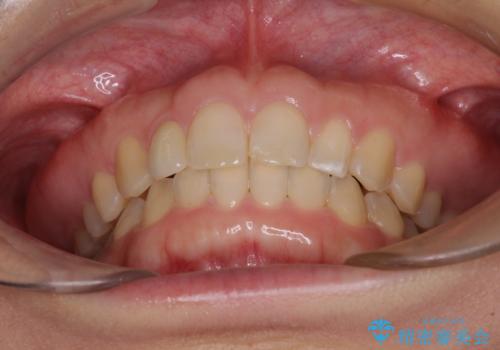

前歯の歯並びと小さい歯を改善 インビザラインとオールセラミッククラウン

- 前歯の空隙と矮小歯を気にして来院された患者様です。

上下の歯列不正はインビザラインにより整えることとしました。

矯正治療の後に、前歯1歯と奥歯をオールセラミックにて治療することとしました。

矯正治療により矮小歯前後にスペースを作りながら歯列を整え、セラミッククラウン装着後に最終的に歯列と咬合を仕上げました。